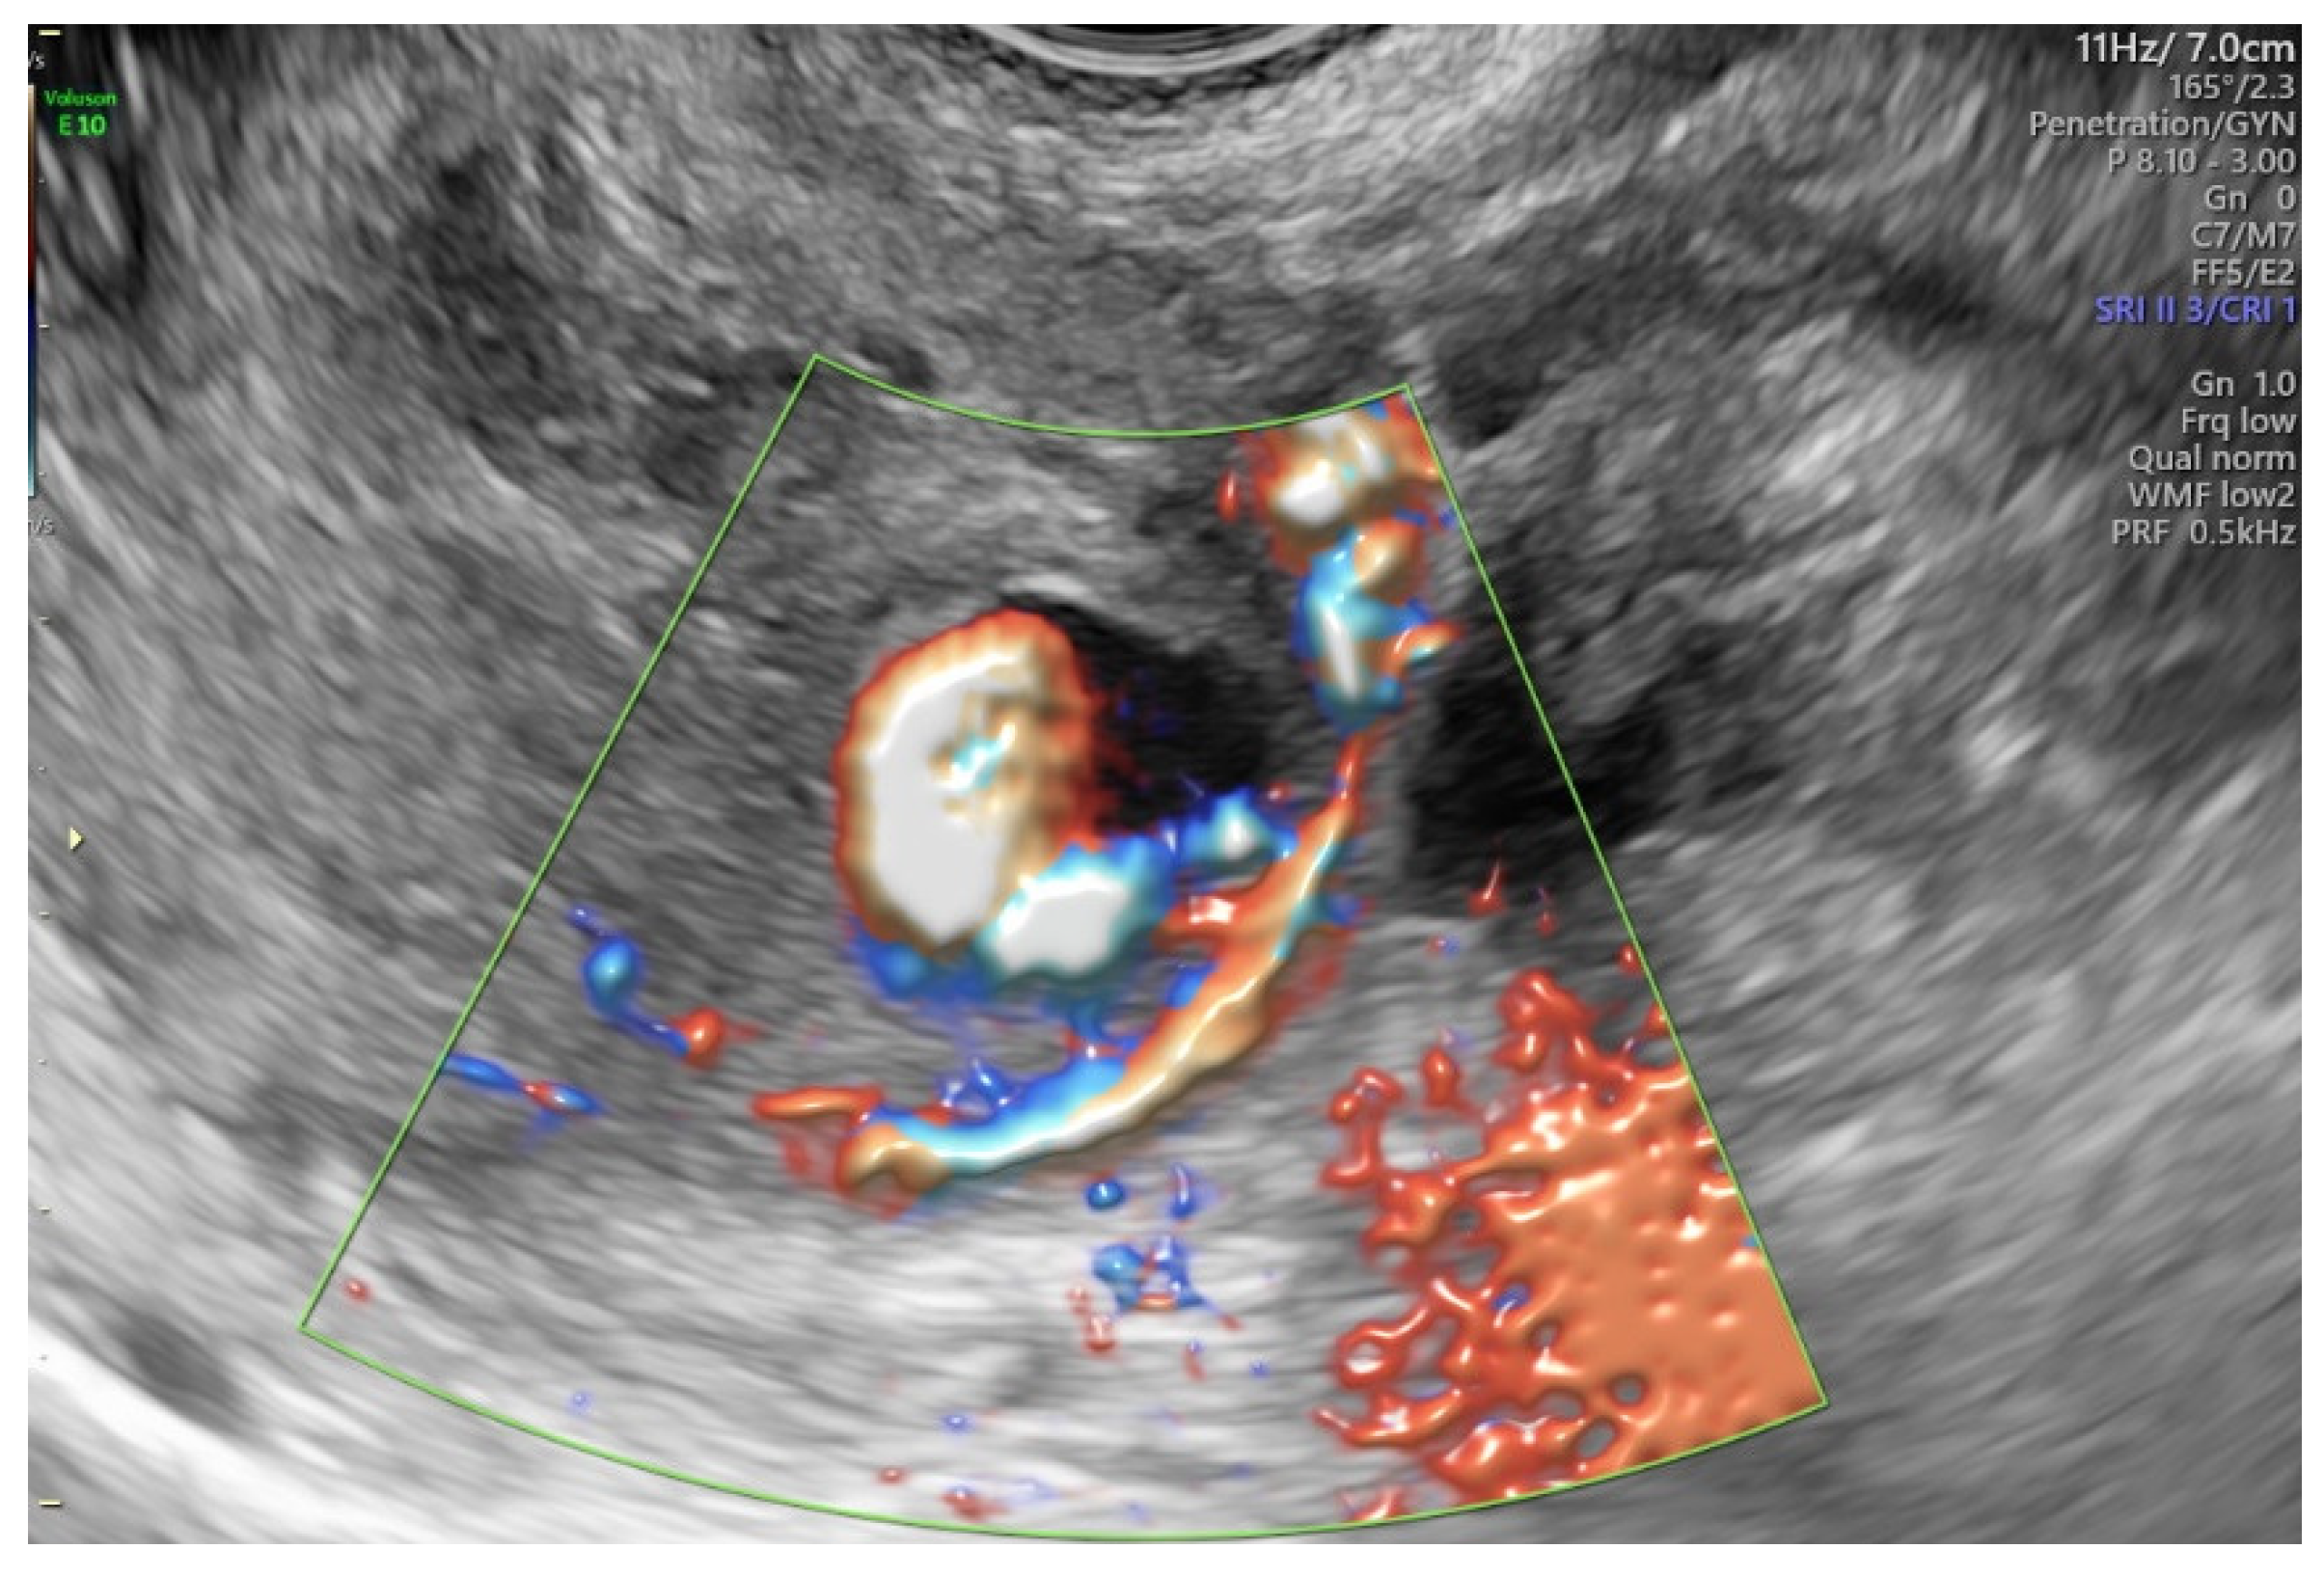

2. Case Report